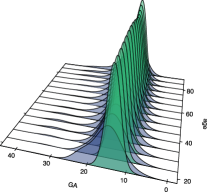

We begin our analysis by representing the conditional densities of the three diagnostic markers at certain ages, along with their corresponding conditional ROC curves. The resulting graphics are collected in Figure 4. Note that the third diagnostic variable appears now under the tab GP22. This is because, in this particular case, higher values of the diagnostic variables are more common in the healthy population, whereas the diseased subjects tend to have lower values, which goes against the assumptions made for the construction of a ROC curve. By taking the opposite values of this variable we ensure that the roles are exchanged.

At first sight it could appear that the conditional ROC curves remain constant through all those values, although we can appreciate a sort of hill for the medium age in the GA marker, and the GP22 seems to have better discriminatory power for the youngest patients, as the conditional ROC curves at those lower ages are closer to the point of maximum sensitivity and specificity.

However, there are two different issues that must be taken into consideration. First, the conditional ROC curve is estimated locally, which means that the estimations computed on the extreme values of the covariate are not as reliable, because they have fewer data around (and this condition exaggerates when the covariate is not uniformly distributed). Secondly, on those representations there is no insight on how the covariate is distributed in the healthy and in the diseased populations.

Next, we estimated the pooled and the covariate-adjusted ROC curves for each one of the diagnostic variables. We represented them in Figure 5. The conditional ROC curve was also estimated for certain values of the covariate, as well as their respective conditional area under the curve (AUC) with a pointwise 0.95 confidence interval (for more details of how to compute such confidence interval, check González-Manteiga et al.,, 2011). The summary measures AUC and area under the AROC curve (AAUC) were also estimated (they are represented as horizontal lines, as they do not depend on fixed values of the covariate).

Setting our attention on those summary measures and the pointwise confidence interval we can have a first insight of the relationship between the curves. For the considered confidence level, the AAUC falls inside the confidence interval for all the values of the covariate, for all the diagnostic markers. Of course, we have to take into account that it is not a confidence band, so the level should be adjusted, but in any case it seems that there may not be differences between those indices. The AUC and the AAUC, despite being presented without confidence intervals, seem to be very similar in the first two variables. The ROC and the AROC curves of GP22, however, are more separated (as their corresponding summary measures are).